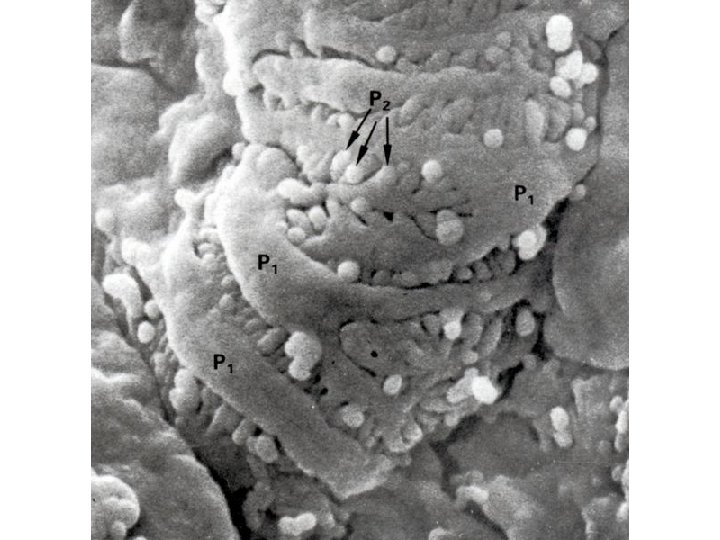

Ledvinné tělísko Corpusculum renale Malpighi • podocyty – trabekuly (cytotrabeculae) – primární výběžky – pedikly (cytopediculi) – sekundární výběžky • bazální membrána • mezangium (mesangium) – mezangiální buňky (mesangiocyti) • fagocytující, kontraktilní a dělící se buňky – mezangiální matrix

Filtrační membrána = bariéra krev-moč (glomerulární filtr) 3 vrstvy: • endotel vlásečnic glomerulu – fenestrace, anionický glykokalyx • bazální membrána – lamina rara interna + lamina densa (kolagen IV, laminin fibronektin, heparan sulfát) + lamina rara externa • pedikly podocytů – anionický glykocaly, interdigitují mezi sebou a tvoří filtrační štěrbiny překryté štěrbinovou membránou – diaphragma rimae (nefrin) - další činitelé: velikost štěrbin (10 nm) a náboj látek → propustí vodu, nízkomolekulární látky → zadrží plazmatické proteiny a krevní buňky